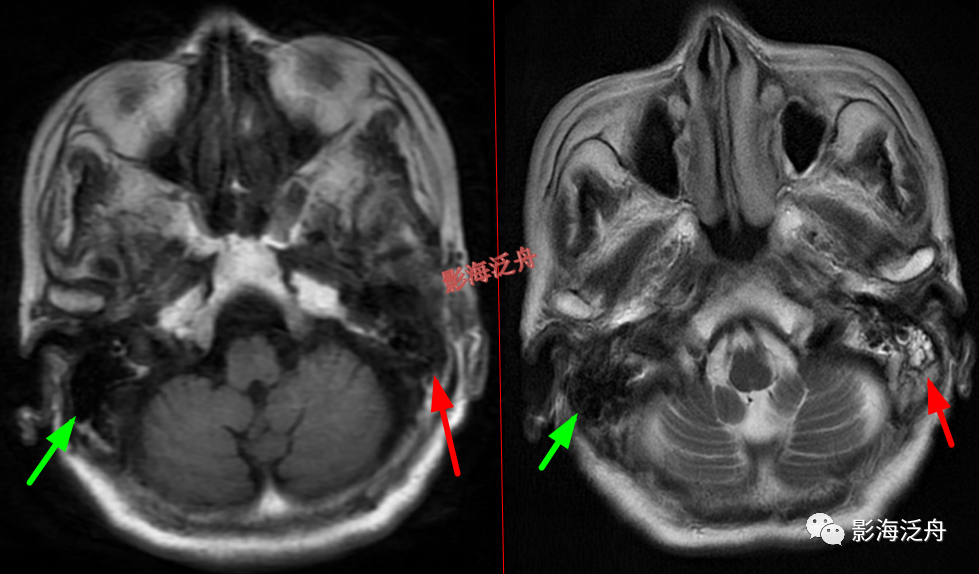

延髓左侧小梗死灶。这种斑点状的梗死灶漏诊也非常多见,患者症状一般不明显,我自己漏诊过两次。小的梗死灶多见于脑干、侧脑室周围,大脑皮层区一般不多见。因此,重点区域进行细致观察,可以减少此类疾病的漏诊。

颞极前方蛛网膜囊肿(红箭)漏诊率也比较高,尤其在老年患者中,常常被误认为是扩大的蛛网膜下间隙,仔细观察可以发现右侧颞叶受压,脑沟闭塞(绿箭),与健侧(蓝箭)对比更为明显。